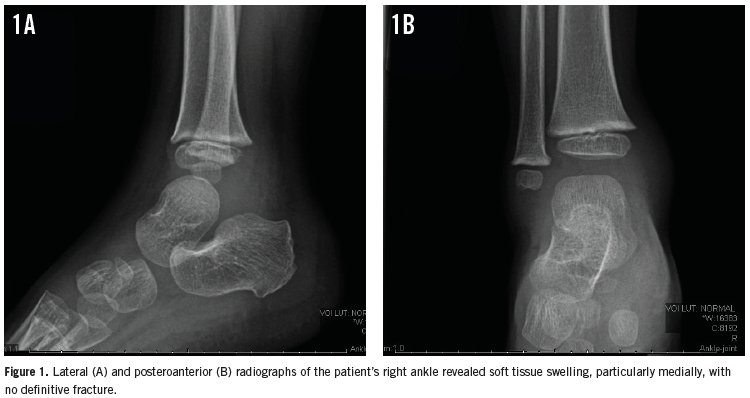

Two days later, he returned to the ER for right ankle pain that had begun after he had descended stairs at home. Radiographs of the patient’s right ankle showed soft tissue swelling but no fracture (Figures 1A and 1B). A preliminary diagnosis of right ankle sprain was made. Out of concern for a possible epiphyseal plate fracture, his ankle was splinted, and he was given ibuprofen for pain and discharged home.